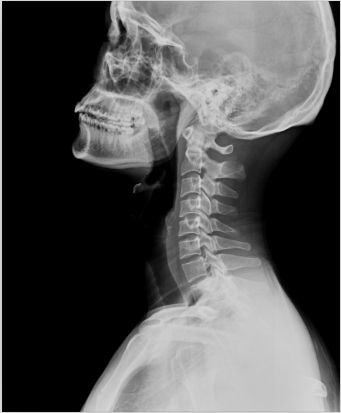

X光攝影(平片)

X光會穿透人體,由于人體各部位組織密度厚度不同,吸收的X光機(jī)的劑量不同,到達(dá)底片的X光的量不同,底片就會顯現(xiàn)出黑白不同的顏色。

優(yōu)點(diǎn):快捷、價廉、影像清晰度高

缺點(diǎn):平片檢查,無法進(jìn)行三維檢查

1、外傷骨頭——粗看X光攝影、細(xì)看CT

當(dāng)遇到各種外傷,如果懷疑傷到了骨頭,優(yōu)先選擇X光攝影,檢查結(jié)果快速易得。若要進(jìn)一步觀察,可以選擇CT觀察細(xì)節(jié),甚至磁共振成像觀察隱匿損傷或軟組織損傷。